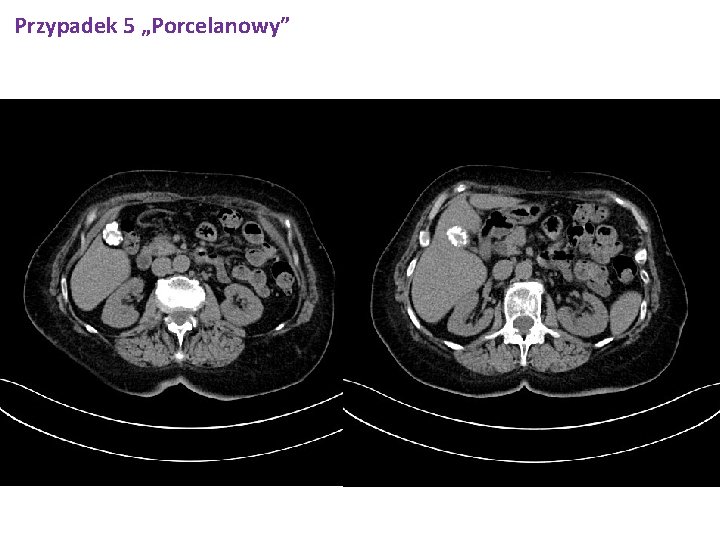

Przypadek 5 „Porcelanowy” 20. 11. 2017 CT jamy brzusznej oraz miednicy. W badaniu zwraca uwagę pęcherzyk żółciowy, którego ściany są inkrustowane wapniem - pęcherzyk porcelanowy; przylegający miąższ wątroby, w otoczeniu loży pęcherzyka prawdopodobnie z cechami nacieku grubości do 7 mm; ponadto widocznie nieznacznie poszerzone gałęzie sektorowe przewodów żółciowych wewnątrzwątrobowych powyżej loży pęcherzyka żółciowego (w segm. 5) oraz zaburzenia perfuzji miąższu wątroby w sąsiedztwie - całość obrazu sugeruje obecność procesu npl w obrębie pęcherzyka żółciowego. Poza tym wątroba niepowiększona, bez zmian ogniskowych. W świetle pęcherzyka żółciowego widoczne uwapnione złogi. PZW poszerzony na całej długości do 14 mm; poszerzone przewody wątrobowe wspólne, prawy do 9 mm, lewy do 5 mm. Trzustka niepowiększona, bez zmian ogniskowych. Przewód trzustkowy nieposzerzony. Obie nerki w położeniu typowym bez zmian ogniskowych, UKM- y bez zastoju. Nadnercza typowego kształtu, wielkości, bez zmian ogniskowych. Śledziona niepowiększona. Naczynia duże jamy brzusznej w normie. Powiększonych węzłów chłonnych nie stw się. Płyn w jamach opłucnych gr. do L - 20 mm, P - 35 mm; powyżej płynu pasmowate obszary zagęszczeń miąższu o charakterze zmian niedodmowych. Struktury kostne objete badaniem bez zmian destrukcyjnych. W macicy endometrium pogrubiałe do 10 mm.

Przypadek 5 „Porcelanowy”

Przypadek 5 „Porcelanowy” Chorą konsultowano ponownie chirurgicznie 21. 11. 2017 (dr Kaczka) - zalecono wyznaczenie planowego terminu przyjęcia do Kliniki Chirurgii za około tydzień (po wyrównaniu hipertyreozy - wartości FT 3, FT 4 powinny być w zakresie normy). Oznaczono ponadto poziom markerów nowotworowych – Ca 125 236. 3, norma do 35), pozostałe markery w normie.

Przypadek 5 „Porcelanowy” q Marker Ca 125 - wartość 236. 3 (norma do 35) q Pęcherzyk żółciowy porcelanowy, miąższ wątroby w ok. pęcherzyka prawdopodobnie nacieczony q Płyn w jamie opłucnowej, zmiany niedodmowe q W badaniu cytologicznym płynu- cellulae atypicae, probaliter carcinomatosae q Pogrubienie endometrium do 10 mm q W lewym płacie tarczycy hypodensyjne zmiany ogniskowe z obecnością zwapnień

Przypadek 5 „Porcelanowy” Pobyt w Klinice Chirurgii Pacjentka przyjęta do Kliniki celem wycięcia pęcherzyka żółciowego - w badaniach obrazowych pęcherzyk porcelanowy. Operowano 15. 12. 17 r. Wykonano cholecystektomię metodą otwartą. Przebieg zabiegu i stan pooperacyjny bez powikłań. Pacjentkę w stanie ogólnym dobrym wypisano do dalszej opieki ambulatoryjnej z zaleceniami. Kontrola i usunięcie szwów w Poradni Chirurgicznej 22. 17 r. Poltram Combo - 4 x dziennie 1 tabletka p/bólowo. Zgłosi się po wynik badania histopatologicznego za ok. 2 tygodnie po wcześniejszym kontakcie telefonicznym z sekretariatem Kliniki. Dalsze leczenie uzależnione od wyniku badania histopatologicznego. Kontynuacja dotychczasowego leczenia chorób towarzyszących. Czas pobytu w Klinice Chirurgii: 14. 12. 2017 -18. 12. 2017 (4 dni)

Przypadek 5 „Porcelanowy” Zabieg operacyjny 15. 12. 2017. rozpoznanie przedoperacyjne Podejrzenie guza pęcherzyka żółciowego. Rodzaj zabiegu Laparatomia. Cholecystectomia. Drainage c. peritonei. operator dr. M. Mordalski dr. T. Matyjas dr Stażysta Po chirurgicznym przygotowaniu pola zabiegu cięciem przezprostnym prawym górnym otwarto jamę brzuszną. Skontrolowano ją Stwierdzono pęcherzyk grubościenny z dużym złogiem. Rozpreparowano więzadło wątrobowo-dwunastnicze , uwidoczniono tętnicę i przewód pęcherzykowy podwiązano je i przecięto. Pęcherzyk usunięto, założono szew hemostatyczny na lożę. Kontrola hemostatzy. Z przecięcia po stronie prawej wyprowadzono drenaż m. operowanego. Szwy warstwowe na powłoki Opatrunek. Dgn. Przewlekłe zapalenie pęcherzyka żółciowego na tle kamicy.